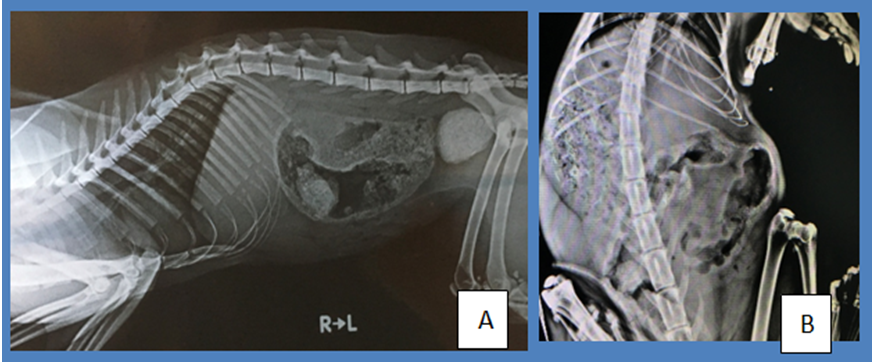

Out of the 9 cats; C1, and C2 cats were with severe constipation (Figure 1&2) after several weeks treatment, C3 had a jaw fracture with severe bacterial infection, C4 had a severe bacterial infection in nostrils and distorted nasal conchae, C5 had a wound on the hind leg with tendon damages and inflammation. C6, C7 were diagnosed to have consequently chronic fungal dermatitis and kidney disease. C8 was diagnosed with gastroenteritis where C9 with upper respiratory tract infection with swollen limb. Clinical signs of cats during presentation were summarized in Table 1. Weight loss and chronic emaciation and chronic multiple infections were a common sign in cats from C1- C9. C1 and C2 with constipation had large intestines comprised of thickened mucosa and sub mucosa which was observed in ultrasound scanning of the abdomen. During the surgery of C1 for removal of clogged fecal ball, enlarged lymph nodes were observed which are adjacent to thickened large intestine. FNA revealed small lymphocytic population which has not converted to a lymphoma. Blood smears of C1, C2, C4 and C9 had higher numbers of lymphoblast population. These lymphoblast’s were overlapped (Figure 3) and identified as monocytosis in dot plot of lymphocytes in the FBC (Procyte IDEXX). Hence, it was seen as monocytosis. Other cats had leukocytosis with neutrophilia due to ongoing bacterial infections (Figure 1–3).

Figure 1 Abdominal radiographs of C1 (A) and C2 (B) with gas filled thickened bowels. B was taken after 3 days of enema and removal of fecal matter of C2.